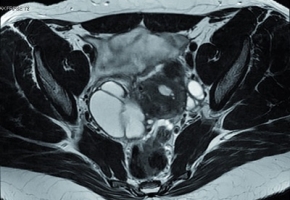

Les symptômes sont par ailleurs évocateurs : dysménorrhée, dyspareunie profonde, symptômes urinaires ou digestifs d’exacerbation cataméniale, infertilité. Les médecins constatant ces symptômes sont incités par les auteurs du rapport à réaliser ou prescrire un examen gynécologique, quand il est possible, qui permettrait la palpation de lésion nodulaire au toucher vaginal (ou rectal) ou visualiser l’atteinte vaginale au spéculum. Enfin, l’imagerie médicale (échographie ou IRM pelvienne) permettra de confirmer le diagnostic. Mais, rappellent-ils, la “réalisation d’une coelioscopie dans le seul but de confirmer le diagnostic n’est plus recommandée”.